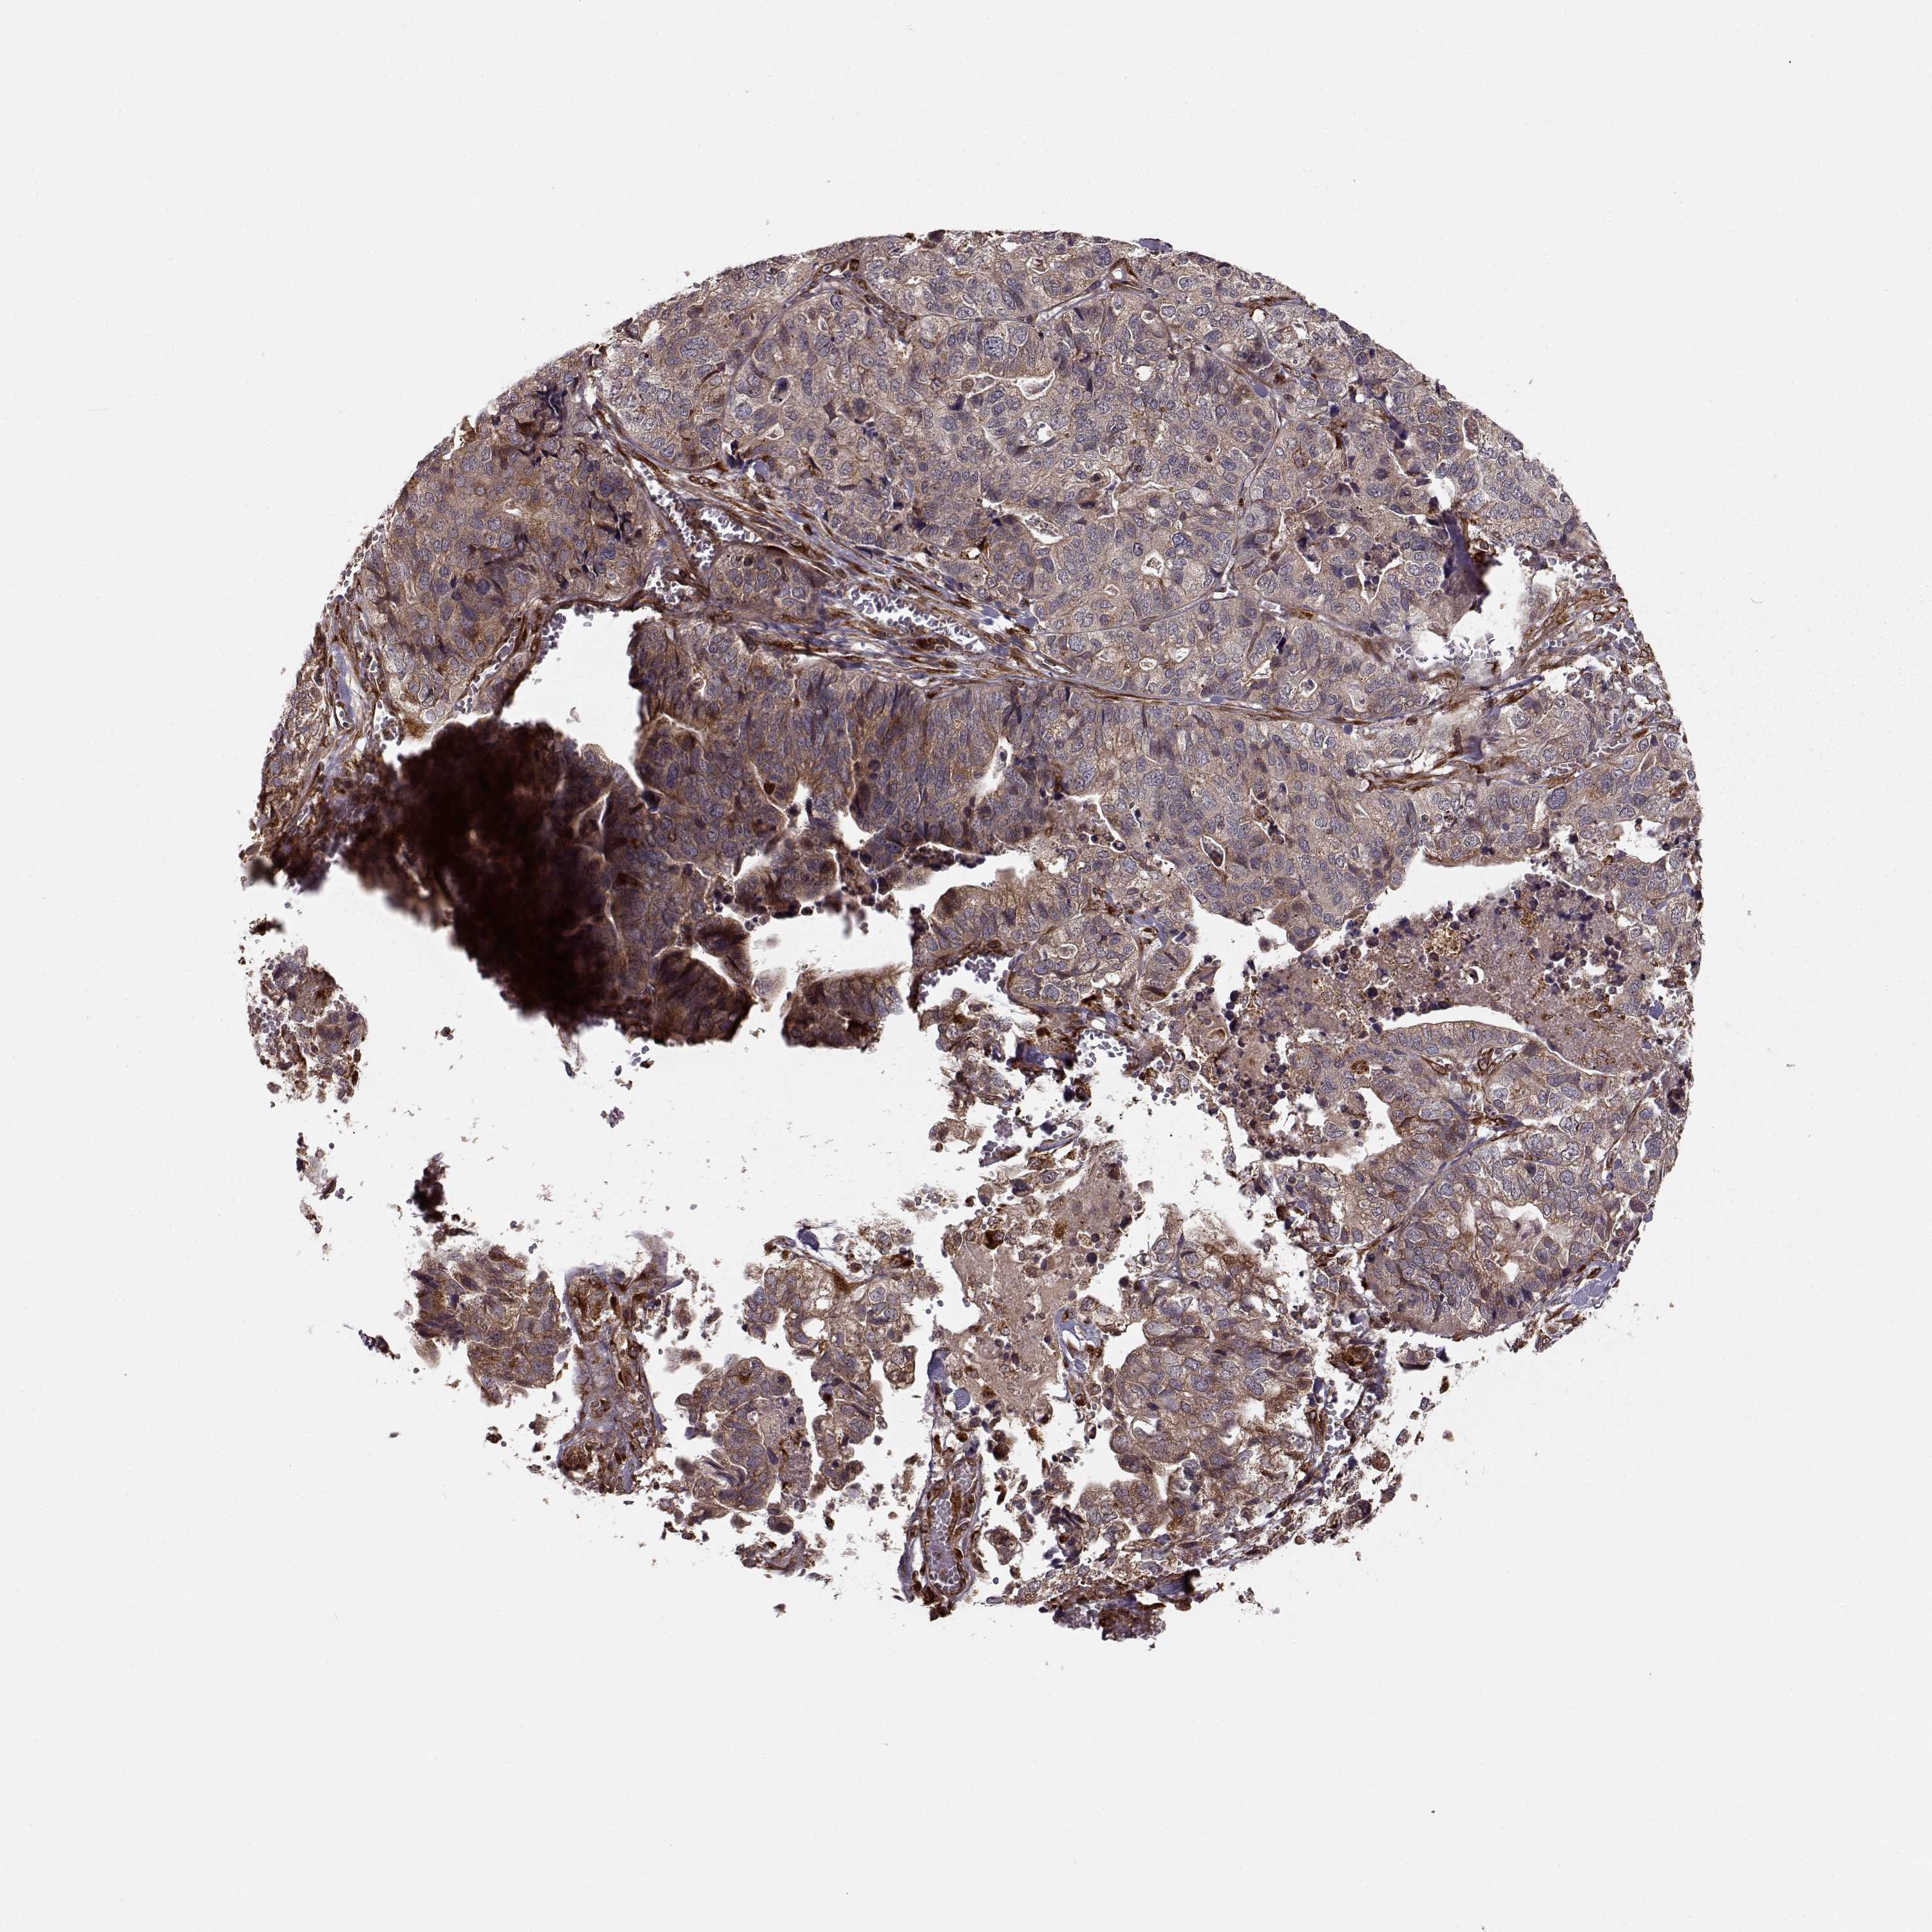

STOMACH CANCER - Protein expressioni

A mouse-over function shows sample information and annotation data. Click on an image to view it in a full screen mode. Samples can be filtered based on level of antibody staining by selecting one or several of the following categories: high, medium, low and not detected. The assay and annotation is described here.

Note that samples used for immunohistochemistry by the Human Protein Atlas do not correspond to samples in the TCGA dataset.

Antibody stainingi

Antibody staining in the annotated cell types in the current human tissue is reported as not detected, low, medium, or high, based on conventional immunohistochemistry profiling in selected tissues. This score is based on the combination of the staining intensity and fraction of stained cells.

Each image is clickable and will lead to virtual microscopy that enables deeper exploration of all samples and also displays staining intensity scores, fraction scores and subcellular localization as well as patient and tissue information for each sample.

Antibody HPA073622

Staining

High

Medium

Low

Not detected

Intensity

Strong

Moderate

Weak

Negative

Quantity

>75%

75%-25%

<25%

None

Location

Nuclear

Cytoplasmic/membranous

Cytoplasmic/membranous,nuclear

Adenocarcinoma, NOS